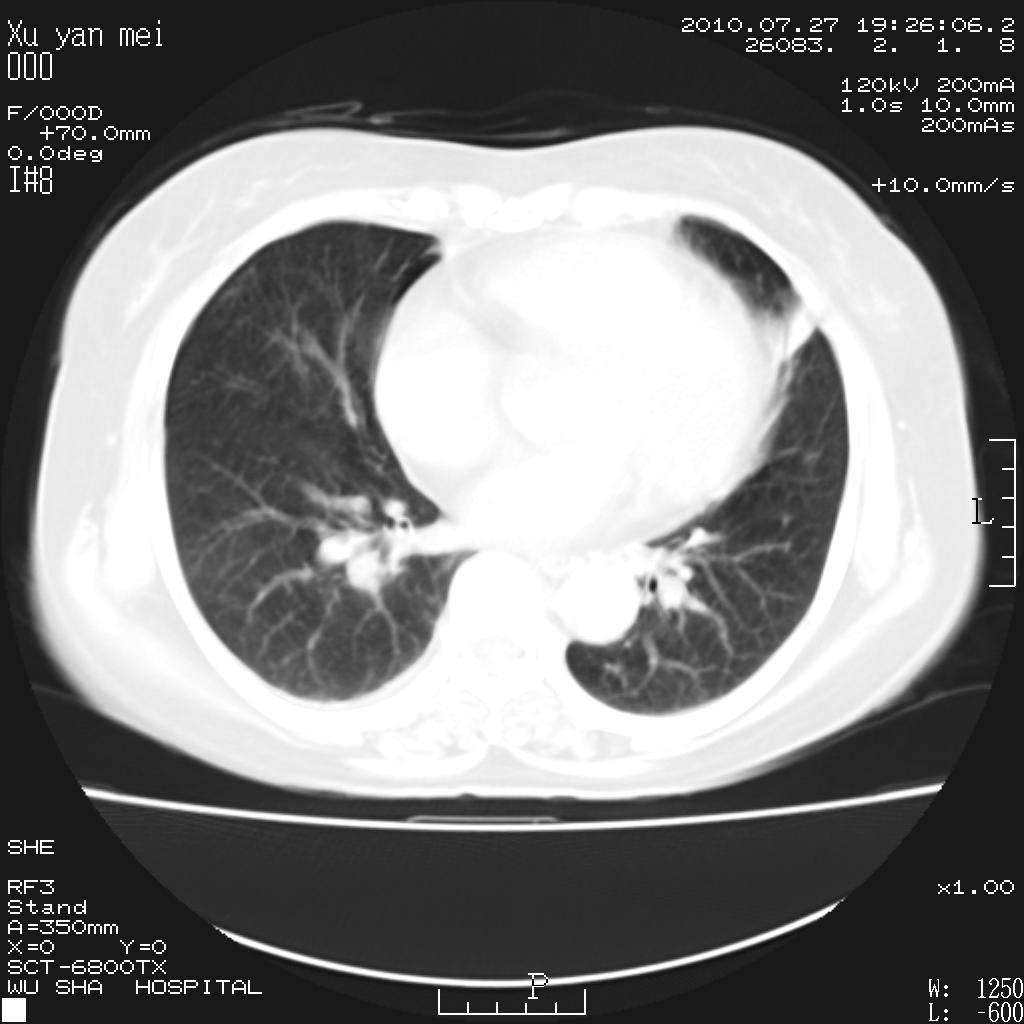

女,60岁,胸痛就诊,右肺结核?炎症?其它?(胸片右侧中上肺野确实看不到什么啊)

1)考虑两肺感染性病变;建议抗炎治疗后复查。2)双侧少量胸腔积液。

1)考虑两肺感染性病变;建议抗炎治疗后复查。2)右侧少量胸腔积液。

双肺炎症可能性大,建议抗炎后复查。右侧胸腔少量积液。双侧胸膜轻度增厚。

考虑两肺感染性病变;不除外肺栓;建议抗炎治疗后复查。